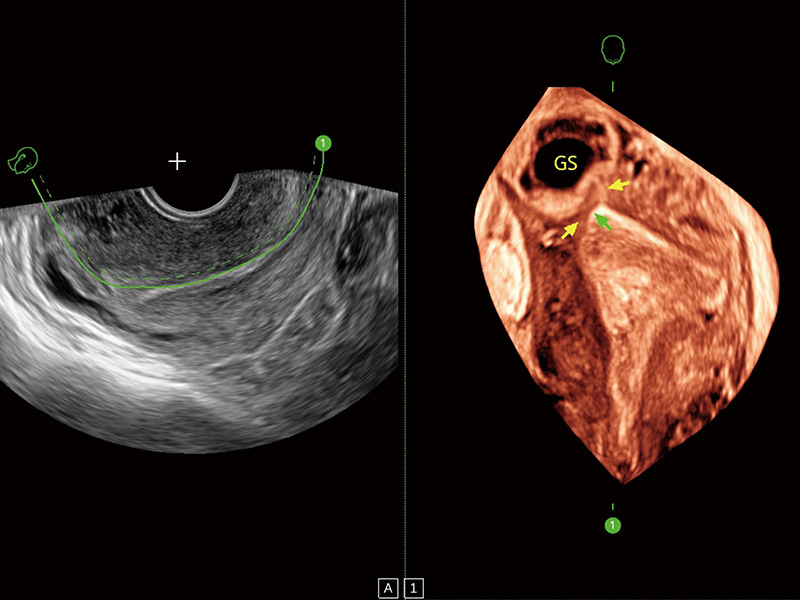

超声引导下胚胎移植

采用弯柄探头替代窥器下叶,巧妙实现了实时超声监控下的单人手术操作。探头频率高、图像清晰,不受肥胖影响,使得手术过程中无需充盈膀胱,即可有效进行胚胎移植、减胎手术的精准操作。